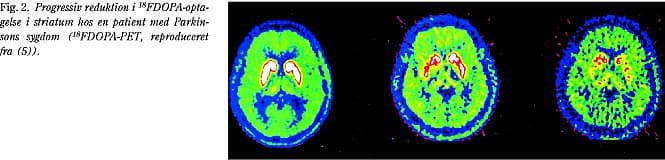

Hos patienter med tidlig IPD findes nær normal 18 F-DOPA-optagelse i nucleus caudatus, men nedsat optagelse særligt i de posteriore dele af putamen (Fig. 2). Dette karakteristiske billede muliggør en komplet distinktion mellem raske forsøgspersoner og patienter med tidlig IPD (6). Ved hjælp af 18 F-DOPA-PET-undersøgelser er det endvidere sandsynliggjort, at omkring 30% af de striatale dopaminerge neuroner skal være gået til grunde, før de første kliniske symptomer viser sig. Det årlige procentuelle tab af striatale dopamintransportere ved tidlig IPD er anslået til at udgøre omkring 12-13%, hvorimod tallene for raske aldersmatchede personer blot ligger på omkring 2% (7), og andre undersøgelser af normale ældre har påvist endnu mindre alderseffekt med typiske tab på 7-10% per dekade (8), hvilket i øvrigt er tæt på det tab, der ses for andre receptorsystemer. Antager man, at der er en lineær sammenhæng mellem tab i enten FDOPA-optagelse i putamen eller dopamintransportermængden i striatum og sygdomsvarighed, kan man beregne, at den prækliniske, asymptomatiske periode, før klinisk manifest IPD viser sig, har en latensperiode på omkring fem år (9). Der er dog visse holdepunkter for, at sygdomsprogressionen hos det enkelte individ relaterer sig til det initiale antal af striatale dopamintransportere.